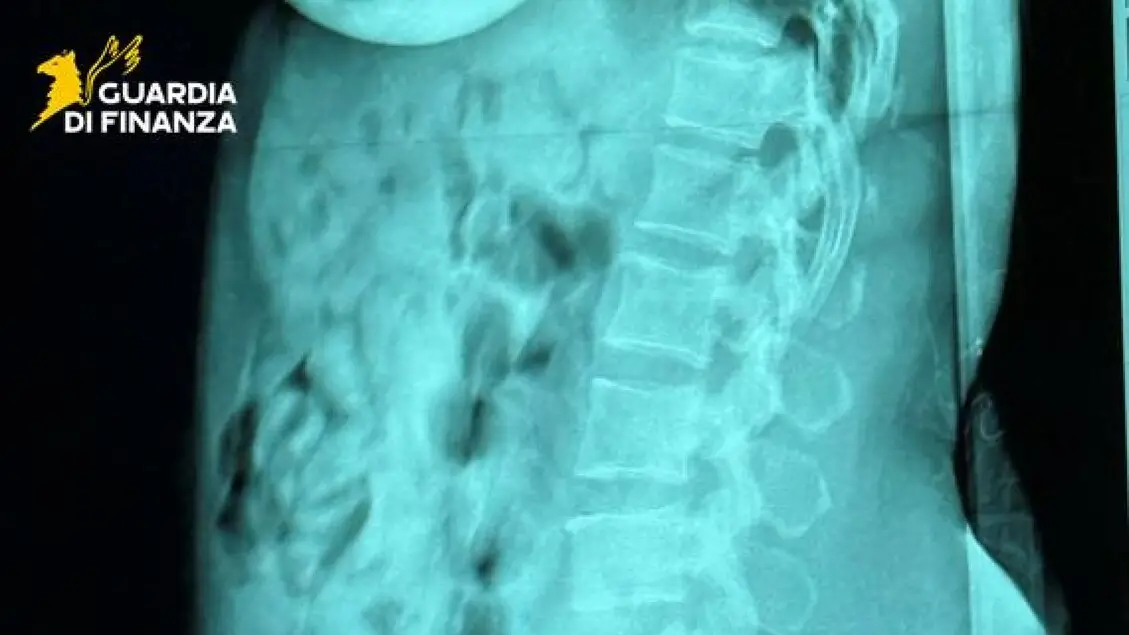

Ingoia 120 ovuli di eroina, passeggera arrestata a Orio

Nello stomaco 1,4 chili di droga, in cella una donna di 46 anni